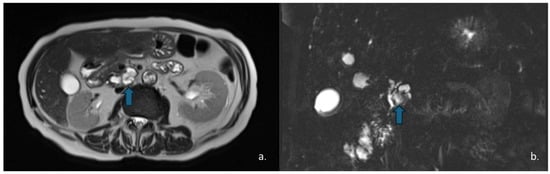

Figure 11.

MRI of a 57-year-old man with neuroendocrine neoplasm (NEN) with cystic degeneration involving the pancreatic body (arrow). The lesion appears hyperintense on T2-w-HASTE sequences (a) and demonstrates peripheral rim-enhancement (b). MR cholangiography shows no communication with the main pancreatic duct (c).